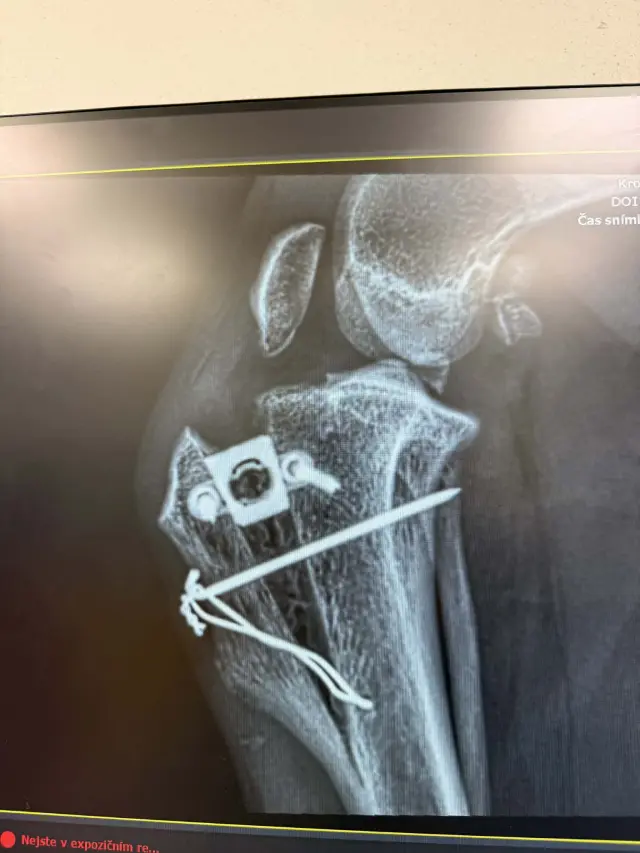

Pomoc pro Kiru – druhá operace přetrženého vazu během pár měsíců

Nešťastný příběh Kiry